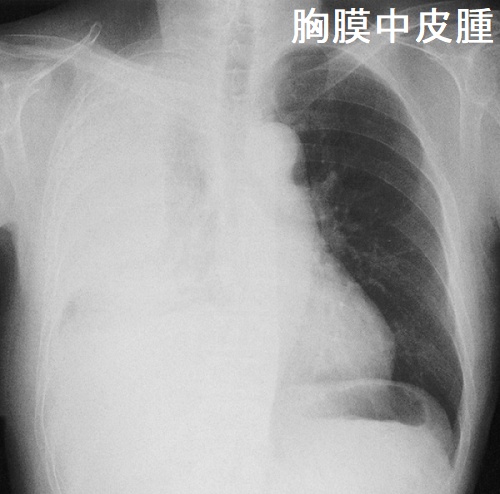

胸膜中皮腫

悪性中皮腫の甲状腺転移

悪性中皮腫のⅣ期には脳、脊柱、甲状腺に遠隔転移します。筆者の経験では、悪性中皮腫の甲状腺転移は、原発巣と同じような粗大な(巨大な)石灰化が見られます。[Pathol Res Pract. 1995 Jun;191(5):456-60; discussion 461-2.]

他の報告では、下記の様に石灰化を伴わない事もあります(Cytojournal. 2014 May 22; 11: 11.)

悪性中皮腫の甲状腺転移では、他臓器にも多発性転移を認めます(Pathol Res Pract. 1995 Jun;191(5):456-60; discussion 461-2.)。